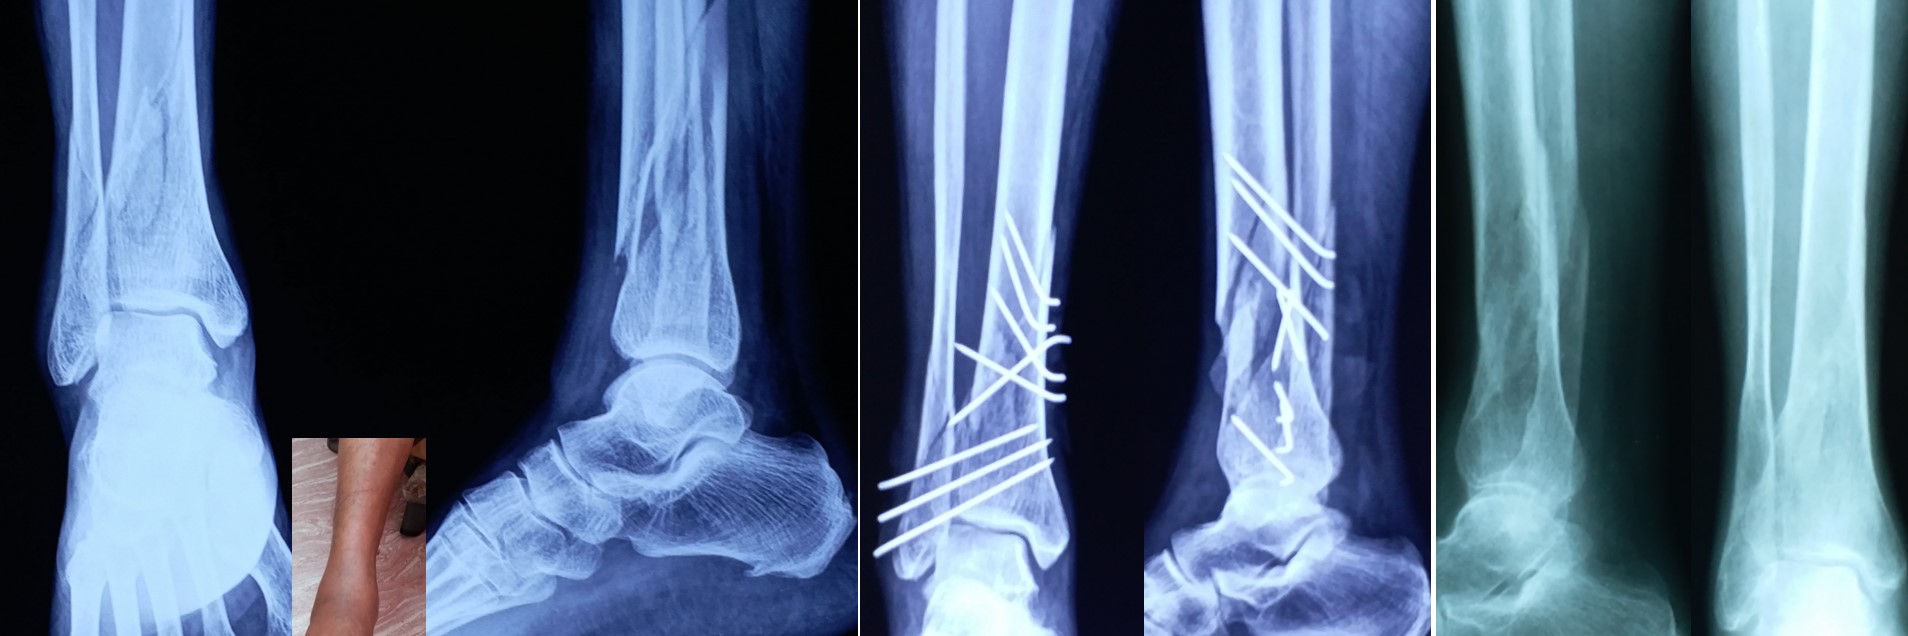

CRPP ( Closed Reduction Percutaneous Pinning )

• CRPP is a minimally invasive surgical procedure under regional anesthesia and the patient can be discharged on the 2nd postoperative day.

• No skin incision is required, and fracture heals faster than open surgeries as there is no iatrogenic soft tissue damage or disturbance to the fracture hematoma.

• No implants projecting outside the skin and hence painless adjacent joint movement is possible immediately after CRPP.

• Most of the metaphyseal fractures of both upper and lower limbs can be successfully treated by CRPP.

• It can be applied to any intraarticular fractures, distal end radius, elbow, ankle and foot.

• It can be applied safely in fractures, where ORIF (Open Reduction Internal Fixation ) cannot be performed or postponed due to impending soft tissue complications.